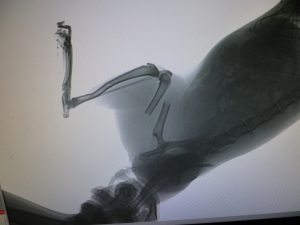

За счет средств Фонда найденной кошке был сделан ренгенолгический снимок, который подтвердил предположительный диагноз -перелом со смещением.

За счет средств Фонда была проведена операция-остеосинтез-хирургическая репозиция костных отломков при помощи специальной спицы, обеспечивающей длительное устранение их подвижности.Цель остеосинтеза — обеспечение стабильной фиксации отломков в правильном положении с сохранением функциональной оси сегмента, стабилизация зоны перелома до полного сращения. Метод является одним из основных при лечении нестабильных переломов длинных трубчатых костей.